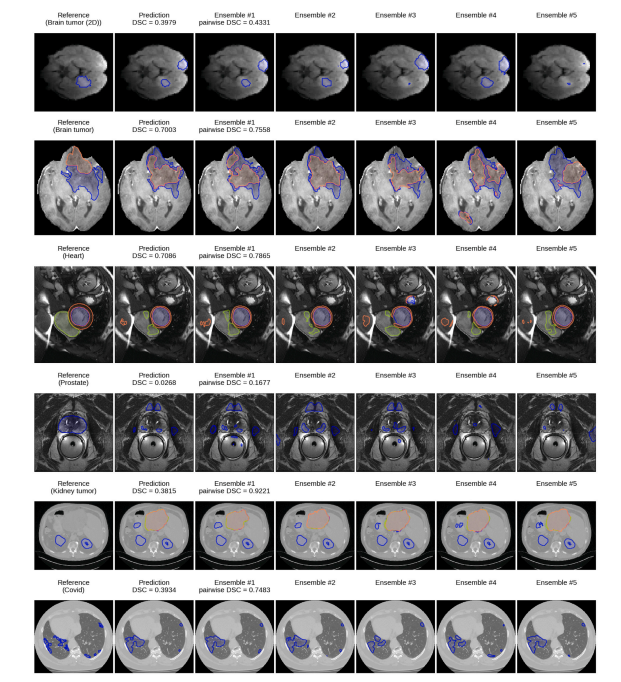

Fig. 6. Qualitative analysis of ensemble predictions on all datasets. For each dataset (rows), an interesting failure case is shown, consisting of (columns from left to right): thereference segmentation, the ensemble prediction and individual predictions of ensemble members (Ensemble #1 – 5) trained with different random seeds. True mean DSC isreported alongside the pairwise DSC scores. The ensemble predictions often disagree about test cases for which segmentation errors occur, which leads to low pairwise Dice andcan be considered a detected failure (rows 1–4). However, there are also cases where the ensemble is confident about a faulty segment, which could result in a silent failure (lasttwo rows).

图6. 针对所有数据集的集成预测定性分析。对于每个数据集(行),展示了一个有趣的失败案例,包括(从左到右的列):参考分割结果、集成预测结果,以及用不同随机种子训练的集成成员(Ensemble #1–5)的单独预测结果。同时报告了真实的平均Dice相似系数(DSC)和成对Dice分数。对于发生分割错误的测试案例,集成预测结果通常存在分歧,导致成对Dice分数较低,可被视为检测到的失败(第1–4行)。然而,也存在一些情况,集成对一个错误的分割结果表现出较高的置信度,这可能导致无声失败(最后两行)。